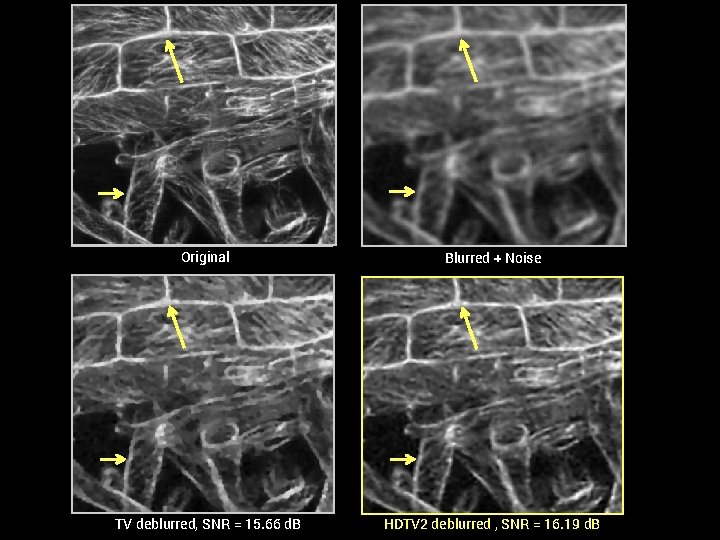

Comparison of HDTV and TV in 2 -D § HDTV routinely outperforms TV for many image recovery problems § Modest increases in computation time (~2 -4 fold) 2 -D TV Comparison. SNR (in d. B) of recovered images with optimal reg. param. (Hu et al, 2014) Denoising Lena Brain Deblurring Cell 1 Cell 2 CS-MRI Brain Wrist TV 27. 35 27. 60 15. 66 16. 67 22. 77 20. 96 HDTV 2 27. 65 28. 05 16. 19 17. 21 22. 82 21. 20 HDTV 3 27. 45 28. 30 16. 17 17. 20 22. 53 21. 02 SNR vs. CPU time of HDTV and TV. (Hu, Y. , & Jacob, M. , 2012) CS-MRI, 2 x accel. CS-MRI, 4 x accel. Denoising, SNR=15 d. B

Original Blurred + Noise TV deblurred, SNR = 15. 66 d. B HDTV 2 deblurred , SNR = 16. 19 d. B